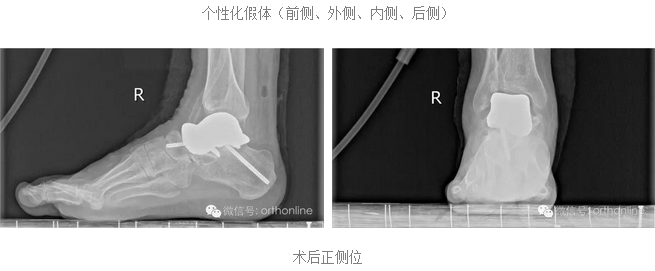

假体个性化特性更为明显:

假体制作完全忠实于患者个体的解剖结构,术前将健侧的骨性解剖数据进行镜像处理,获得个性化假体数据源;3D打印完成后再将假体扫描,与数据源进行耦合对照检测;假体植入后扫描患肢,检测与数据源耦合性能;

根据距骨不同部位力学需求,选用力学性能匹配的金属材料和打印方式,完成力学性能的个体化。突破踝关节置换的禁忌: